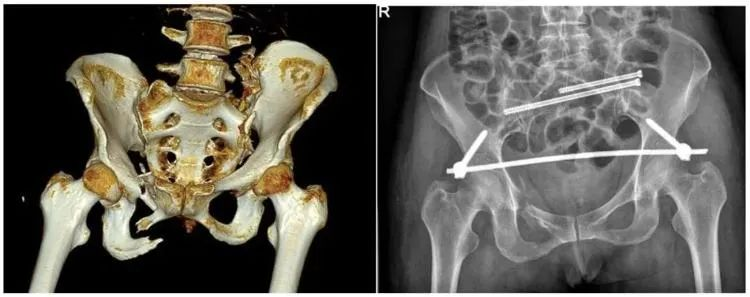

不穩(wěn)定性骨折

普愛醫(yī)療推出的大平板一體式C形臂PLX119C,配置30cm×30cm平板探測器,大視野,能夠呈現(xiàn)更多圖像細(xì)節(jié),對于諸如骨盆雙側(cè)骨折類型手術(shù)或骨盆后環(huán)內(nèi)固定術(shù)具有應(yīng)用優(yōu)勢,一次曝光可獲取全部骨折部位影像,可簡化曝光流程,提高手術(shù)效率。